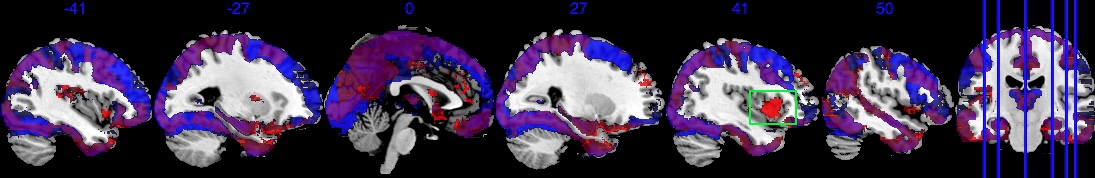

In addition, Figure 6 shows results equivalent to those in Figure 3, but with the selection indicator applied simultaneously to both the main effect and the interaction effect. As shown in Figure 6(b), the posterior of in model (10) is driven by both and . The regions exhibiting strong negative effects of do not fully align with the regions showing , in contrast to the original results in Figure 3(b). Therefore, if the primary interest is in the main exposure variable , such as age in our analysis, we recommend applying exclusively to this primary effect to achieve a more accurate selection of activation regions.

Since the gender variable is binary with female being 0 and male being 1, the interpretation for is that comparing to the female subjects, one standard deviation (s.d.) increase in age for male subjects is associated with -s.d. of change in the image intensity. The boxed green area in Figure 6(c) and Figure 6(b) identifies one active area where has a negligible effect, but has a large effect size, indicating that this area is associated with the differences of male’s age-brain intensity association compared to female. For example, one s.d. increase in male’s age is associated with at least 0.01 s.d. increase in brain signal intensity compared to the female baseline in this green-boxed area. On the other hand, Figure 6(d) also identifies areas where one s.d. increase in male’s age is associated with at least 0.01 s.d. decrease in brain signal intensity compared to the female baseline. The area in the green box spans several brain regions in the right hemisphere, including Right lateral occipital cortex, superior division, Right insular cortex, Right middle temporal gyrus, posterior division, and Right frontal operculum cortex. They jointly integrate information from multiple modalities and detect behaviorally relevant stimuli. The negative in Figure 6(d) spans over Right parahippocampal gyrus, posterior division, Right temporal fusiform cortex, posterior division, Left temporal fusiform cortex, posterior division, Left temporal pole. They jointly process and integrate vision and semantic information and are related to contextual and memory functions.